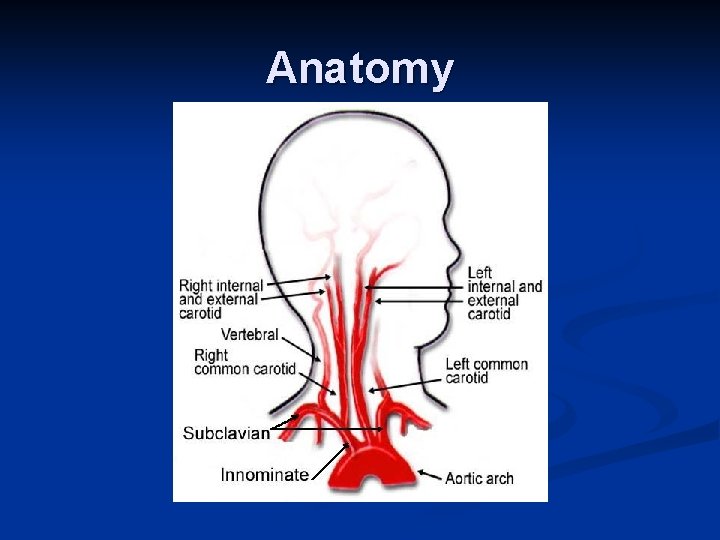

Anatomy n Aortic Arch n Innominate or Brachiocephalic artery n Right subclavian artery n Right common carotid Left common carotid artery n Left subclavian artery n n CCAs lie posterolateral to thyroid n Deep to sternocleidomastoid muscle n

Anatomy Right CCA originates from innominate artery n Left CCA originates from aortic arch n CCAs divide into ECA and ICA n ICA has no branching vessels in the neck; may have slight dilation just past its origin; supplies face and head; lies posterior in the neck n ECA has branching vessels; usually smaller than ICA n n Vertebral Arteries – lie between transverse